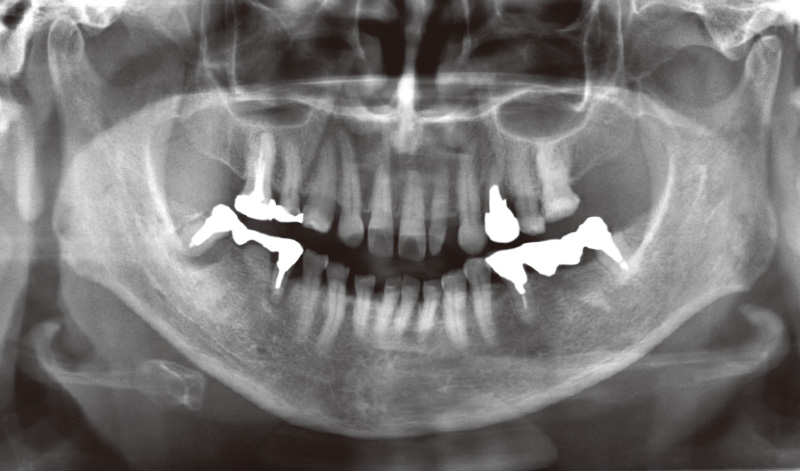

患者は73歳女性。主訴は「左上奥歯が食べ物をかむと痛む」とのこと。診査の結果、上顎左側第一小臼歯 (24)に慢性的な歯周炎と、根尖部透過像や歯根膜腔の拡大、歯根破折が認められた。40年以上前に治療を受けた既往歴があり、炎症の状況により患者抜歯後の即時インプラント埋入をその場で判断し行うこととなった(図1)。

図1 術前パノラマX-P(Veraview X800にて撮影) -